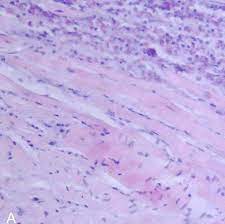

심근염(Myocarditis)은 심장 근육인 심근의 염증을 나타내며, 주로 바이러스, 박테리아, 기생충, 약물 반응 등의 인자로 인해 발생합니다. 이 염증은 심근 조직의 염증 세포와 면역 반응의 과도한 활성화로 인해 발생할 수 있습니다. 심근염은 심장 기능의 변화를 초래하며, 심장 파괴와 심부전과 같은 심각한 합병증을 유발할 수 있습니다.

심근염의 진단은 심전도, 혈액 검사, 심장 자기 공명영상(MRI) 등을 활용하여 염증의 증거를 확인합니다. 치료는 주로 염증의 원인에 따라 달라지며, 항염증 약물, 휴식, 증상 관리 등이 사용될 수 있습니다. 이 질환은 의료 전문가와의 상담을 통해 정확한 진단과 적절한 치료가 이루어져야 합니다.